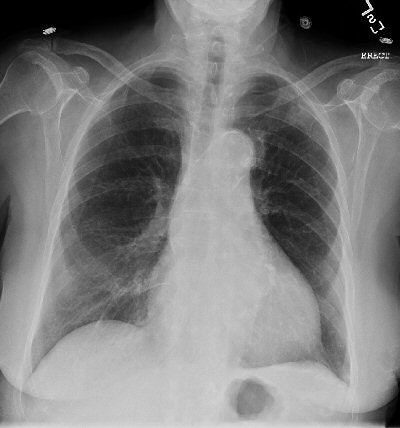

Dr. Anthony Garritano, a visiting radiologist at the Department of Veterans Affairs Medical Center in Bay Pines, FL, uses six images as part of his dual-energy subtraction process with CR. After the two initial images -- a standard posteroanterior (PA) and lateral (frontal and side) view -- are obtained, Garritano uses CR to create four additional images -- a PA and lateral view of the tissue, and an additional PA and lateral of bone structures -- which adds no time or expense to the process. The value of the varying perspectives is detecting abnormalities, lesions, or cancers that could be hidden behind a bone.

"When you are looking at x-rays, you are looking through everything -- the bone, the lungs -- on chest x-rays," Garritano said. "It is quite possible for a tiny lesion to be behind a bone, but not dense enough to see on a routine x-ray until you get the bone out of the way."

When dual-energy subtraction eliminates the bone structure, small cancers can be seen. "If it weren't for dual-energy subtraction imaging, we would not have seen those (lesions) until they got bigger, and then you're running into problems with the patient, because the cancer has been growing," Garritano said.

In other cases, there may be a small lesion between the ribs. If the lesion is smaller than 5 mm, it may go undetected on a standard x-ray image. Another dual-energy subtraction benefit is in detecting suspicious rib fractures or rib lesions that are quite small, possibly invisible to standard rib x-rays, because of the obstruction of other soft tissue.

| Above: PA chest radiograph of an 86-year-old female. Below: Dual-energy subtraction image of figure above. The subtle left upper lobe mass is demonstrated (arrow). |